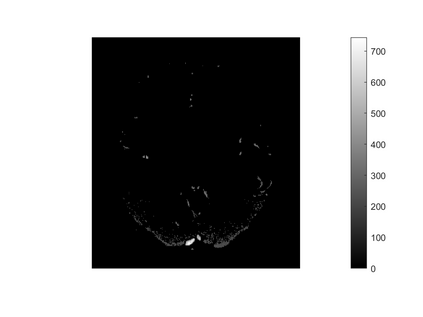

One of the most prominent methods for uncertainty quantification in high-dimen-sional statistics is the desparsified LASSO that relies on unconstrained $\ell_1$-minimization. The majority of initial works focused on real (sub-)Gaussian designs. However, in many applications, such as magnetic resonance imaging (MRI), the measurement process possesses a certain structure due to the nature of the problem. The measurement operator in MRI can be described by a subsampled Fourier matrix. The purpose of this work is to extend the uncertainty quantification process using the desparsified LASSO to design matrices originating from a bounded orthonormal system, which naturally generalizes the subsampled Fourier case and also allows for the treatment of the case where the sparsity basis is not the standard basis. In particular we construct honest confidence intervals for every pixel of an MR image that is sparse in the standard basis provided the number of measurements satisfies $n \gtrsim\max\{ s\log^2 s\log p, s \log^2 p \}$ or that is sparse with respect to the Haar Wavelet basis provided a slightly larger number of measurements.